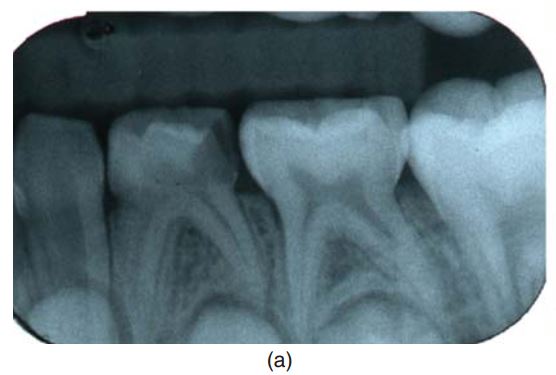

Nên chụp một phim quanh chóp trước điều trị để loại trừ nhiễm trùng, nội ngoại tiêu chân răng, đánh giá mức độ phát triển của chân răng (H6.2a).

Chân răng sữa thường rất mảnh, nếu có nội ngoại tiêu chân răng thì nên chỉ định nhổ (H6.2 b).